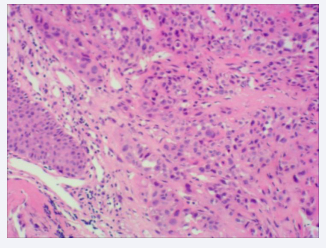

Biopsies were obtained during bronchoscopy at the opening of the middle and lower lobes, and bronchoalveolar lavage was performed on the lower lobe of the right lung. The culture and cytology of the bronchoalveolar lavage fluid were negative. A set of biopsy specimens, stained with hematoxylin and eosin (HE), indicated SCC in the right middle lobe and an inflammatory response in the lower lobe of the right lung (Figures 3,4).

HE staining of the tissue obtained from the right middle lobe  of the right lung (×100).

Figure 3: HE staining of the tissue obtained from the right middle lobe of the right lung (×100).